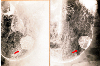

症例提示(所在地,施設名等): 東京都・ 国立がんセンター中央病院と九州がんセンターの共同作成

症例登録日 2000/03/14

病理学分類悪性上皮性腫瘍/腺癌

備考3866